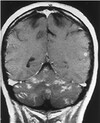

You see a patient with this MRI. What histologic findings would you expect if this was found to be a glial neoplasm?

What is the diagnosis? A. Holoprosencephaly B. Agenesis of the corpus callosum C. Polymicrogyria D. Agyria

A. Holoprosencephaly B. Agenesis of the corpus callosum **C. Polymicrogyria** D. Agyria ## Footnote This brain demonstrates polymicrogyria, a condition that can be asymptomatic, or cause severe mental retardation if the involvement is throughout the cortical surface of the brain. Further Reading: Psaaros. The Definitive Neurosurgical Board Review, page 110.